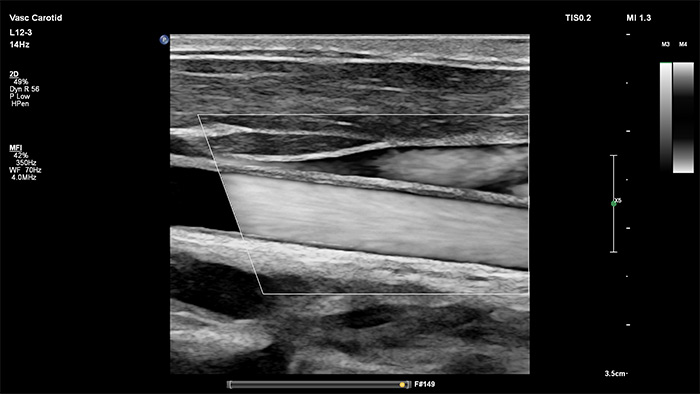

Philips MicroFlow Imaging è concepito per rilevare con considerevole sensibilità il flusso di sangue lento e debole nei tessuti e migliorare la risoluzione del flusso in esami vascolari. Grazie alla risoluzione elevata e agli artefatti ridotti al minimo, i medici sono in grado di visualizzare e caratterizzare piccole alterazioni del flusso attorno alla placca stenotica per formulare diagnosi affidabili.